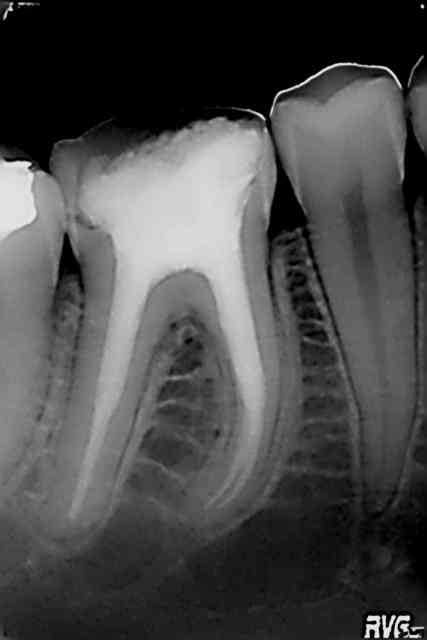

J'ai terminé la moitié de ma boite de gutta avec ce patient .

Img 5415 n0e23w - Eugenol